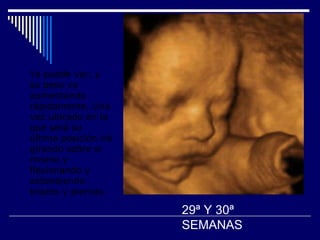

Ya puede ver, y su peso va aumentando rápidamente. Una vez ubicado en la que será su última posición irá girando sobre si mismo y flexionando y extendiendo brazos y piernas   29ª Y 30ª SEMANAS

Ya puede ver,y su peso va aumentando rápidamente. Una vez ubicado en la que será su última posición irá girando sobre si mismo y flexionando y extendiendo brazos y piernas 29ª Y 30ª SEMANAS